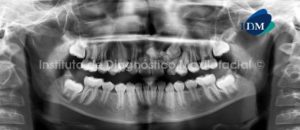

Paciente masculino, 56 años de edad acude a Imágenes Digitales (COREF) en Santo Domingo para evaluación tomográfica debido a que presenta supuración a nivel basal